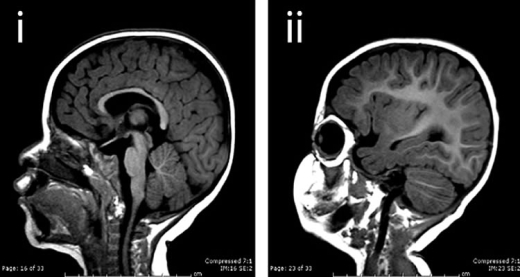

Imagem em Medicina: Paracoccidioidomicose

Lesão verrucosa de face e linfonodial de várias cadeias. Biopsia de linfonodo com presença de paracoco. RX de torax normal